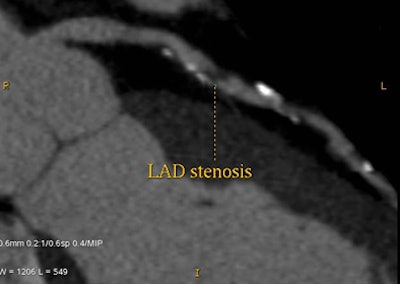

| Stenosis in left anterior descending artery detected at CT angiography (above) is confirmed at angiography (below). Images courtesy of Dr. Matthew Budoff. |